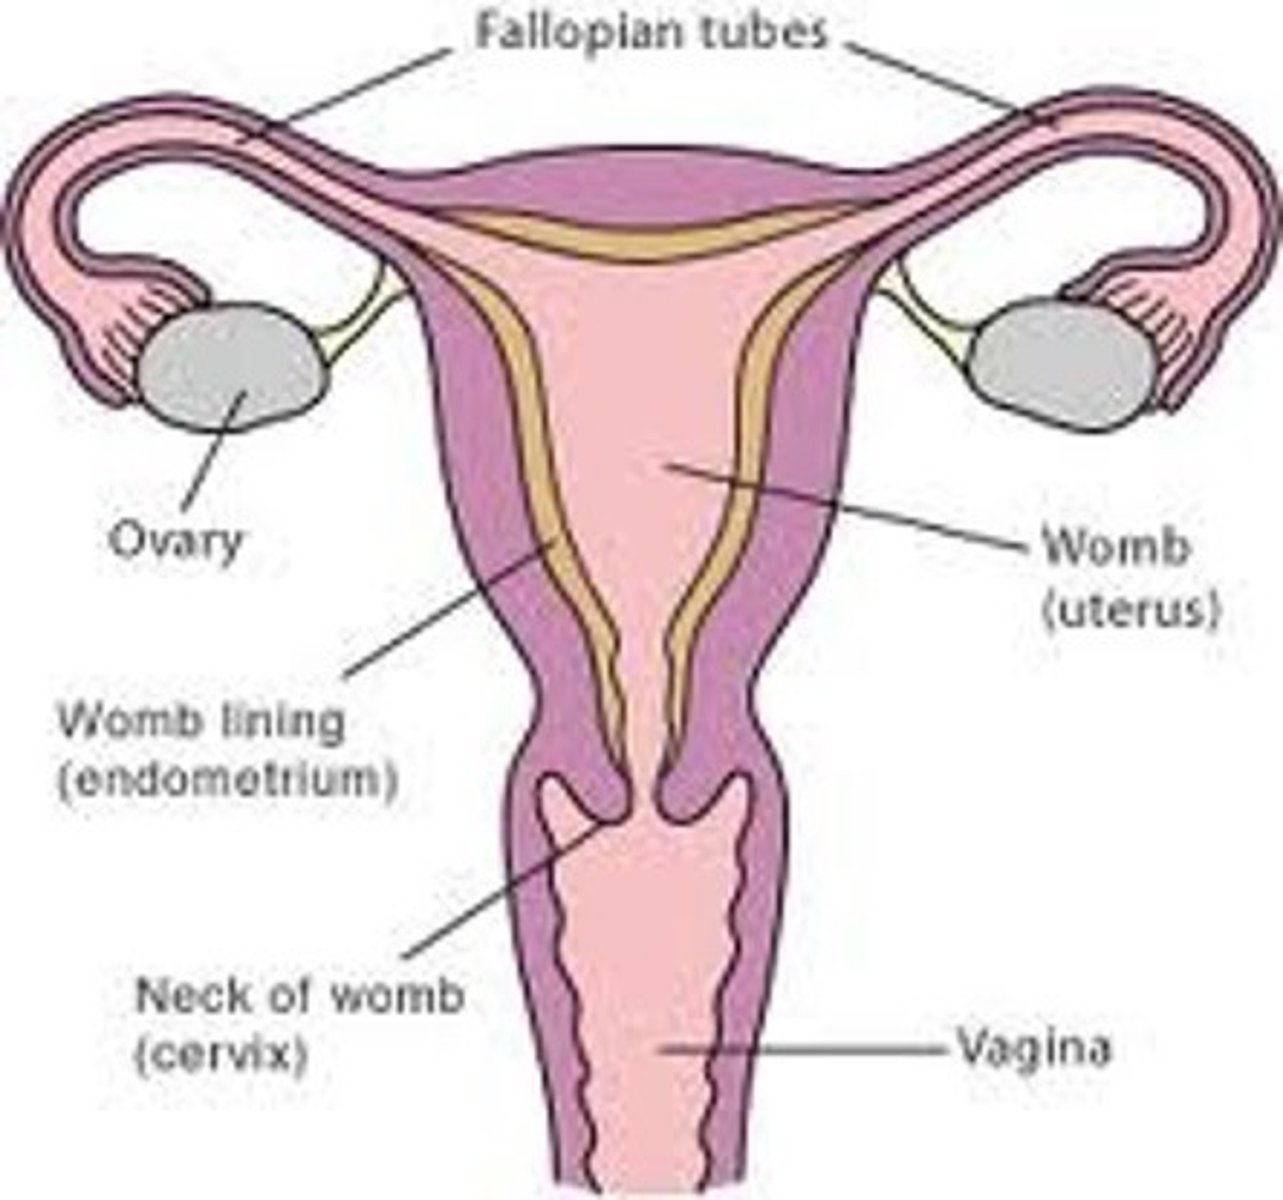

What are the 3 layers of the uterine walls?

inner- endometrium

middle- myometrium

outer- serosa

What is serosa also called?

perimetrium

The endometrial cavity is continuous with the ___

vaginal canal

What is the widest and most superior part of the uterus?

fundus

What is the largest part of the uterus?

corpus / body

What is the uterine isthmus also called?

lower uterine segment

The cervix is ___ long

2 to 4 cm